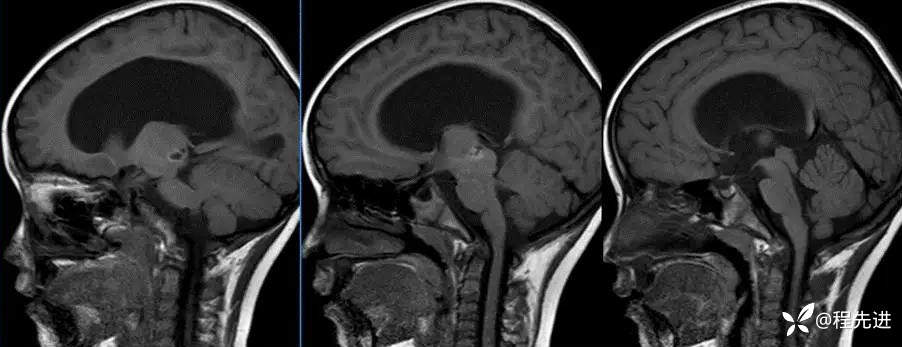

MR